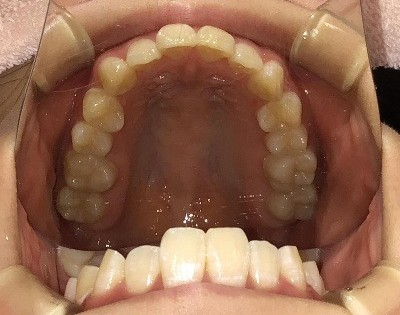

• BEFORE

症例集 インビザライン 上顎

矢印

AFTER

上顎